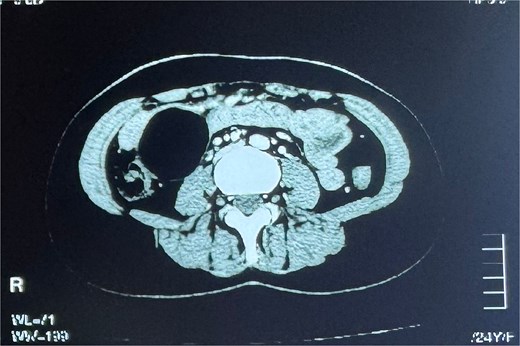

Biochemical tests were normal. Ultrasound revealed a 56 × 52 mm right sub-hepatic cystic lesion, likely a mesenteric cyst. CT confirmed a 5.2 × 4.9 cm well-defined cyst with enhancing walls, abutting small bowel loops (Fig. 1).

Contrast-enhanced CT scan of the abdomen showing a well-defined, rounded cystic lesion with enhancing walls in the right hemi-abdomen, abutting adjacent small bowel loops.

Common investigations involved in the management of a case of mesenteric cyst include transabdominal ultrasonography and a Computed Tomography scan, which are useful in visualizing the location of the benign cyst. An abdominal X-ray or magnetic resonance imaging (MRI) may also be performed for investigation [2, 12]. We performed a transabdominal ultrasonography, which showed a right sub-hepatic cystic lesion. A subsequent contrast-enhanced CT scan also helped visualize a well-defined, rounded cyst lesion with enhancing walls in the right hemi-abdomen, measuring 5.2 x 4.9 cm.